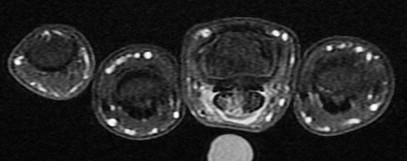

Figure 2 for case gout arthritis ( RID3567 )

Figure 2

Flexor tenosynovitis, tendon infiltration and also 2nd MCP synovitis with subtle reactive osteitis and early erosive change. My differential was RA vs gout. This is proven gout.